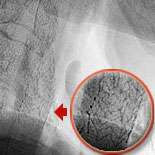

Fig 3: The inflation of the carotid filter balloon opens up Ralph's narrowing left carotid artery.

Fig 4: A stent, which is a metallic cage, is placed in the artery to keep it opened.

The cutting edge treatment is to insert a carotid filter balloon which is an umbrella like device used to catch debris as the artery is being opened. Fig.1 shows Ralph's narrowing of the left carotid artery. Fig.2 shows the device being inserted in Ralph's artery. In fig.3 the carotid balloon's up showing inflation of the balloon which opens the blocked artery. A stent (fig.4) which is a metallic cage is placed in the artery to keep it opened.